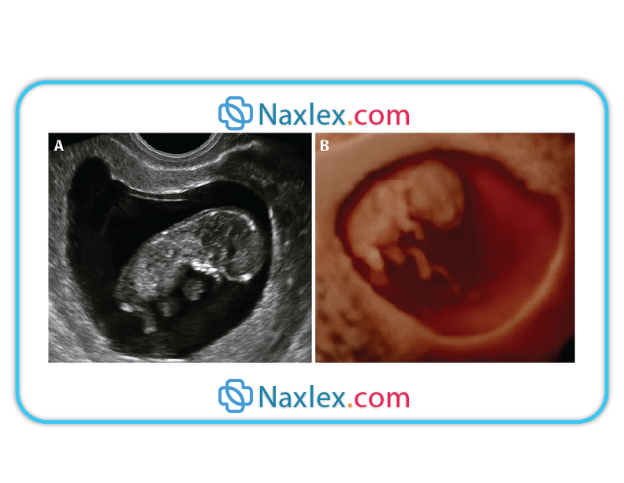

4.Visualization of the fetus by ultrasound is a positive sign. Seeing the embryo or fetus with cardiac activity confirms intrauterine pregnancy. Cardiac motion can be seen by transvaginal ultrasound at approximately 5–6 weeks.

3.Ultrasound visualization of the fetus provides indisputable evidence of pregnancy. Gestational sac can be seen by 5 weeks, and fetal pole with cardiac activity by 6–7 weeks.

• Ultrasound Visualization of Fetus: Transvaginal ultrasound can detect a gestational sac as early as 4-5 weeks and confirm fetal cardiac activity by 6-7 weeks, providing definitive evidence of pregnancy.